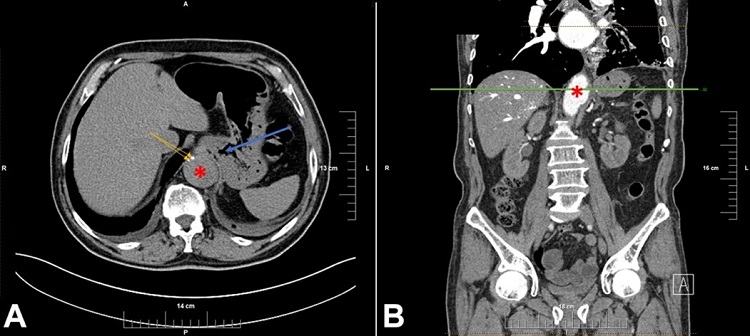

Previous medical history included pulmonary thromboembolism two months prior, when two AAA were reported on abdominal CT, both were fusiform, with the first one just below the diaphragm with a diameter of 40mm and a second one, 3mm below the left renal artery, with a diameter of 34mm (Figure 1). The patient was prescribed anticoagulant therapy, but did not follow up the treatment regimen.